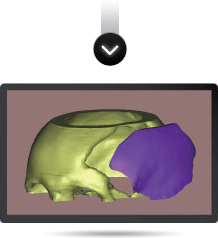

La reconstrucción utiliza como información de entrada imágenes obtenidas por técnicas de diagnóstico (TAC o MRI). A través de un software especializado se procesan las imágenes y se logra modelar en tres dimensiones cualquier región anatómica con patologías diversas.

En el modelado 3D digital se pueden incluir implantes ortopédicos como placas, tornillos, mallas, prótesis, etc., y también modelados en 3D y en tamaño real en relación con el modelo anatómico. De esta forma es posible simular diferentes situaciones con las que el cirujano se enfrentará durante el proceso quirúrgico.

Una vez obtenida la información de la TAC o MRI y modelado el 3D digital, podemos modelar la prótesis que se necesita (por ejemplo, una porción de calota faltante) y posteriormente realizarla en resina plástica. De esta manera validamos la adaptación del futuro implante a la anatomía. El cirujano puede verificar las imágenes modeladas digitalmente o el prototipo en resina plástica, y sugerir modificaciones dando paso al proceso final.

Se aplica un programa informático validado para convertir y manipular la información de la TAC y crear un modelo de implante anatómicamente correcto.

Antes de la fabricación del implante, el cirujano puede elegir entre dos métodos de examen del implante PROTOLAB: 1) Un modelo del cráneo y del implante para ser examinado, marcado o aprobado;

2) Las imágenes informáticas del defecto, del implante y de éste acoplado en el defecto enviadas por medios electrónicos.